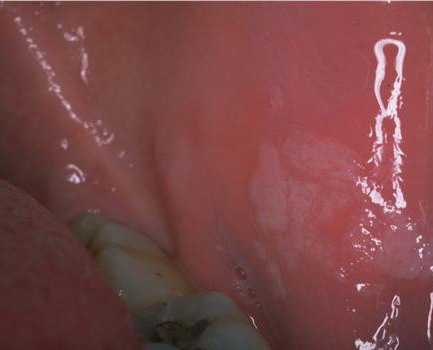

Leucoplakia Praecancerosa = الطلاوة ماقبل السرطانية